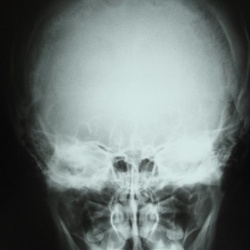

Девушка, 26 лет, после травмы головы направлена на рентгенографию черепа. Ваши мнения? Есть ли патология?